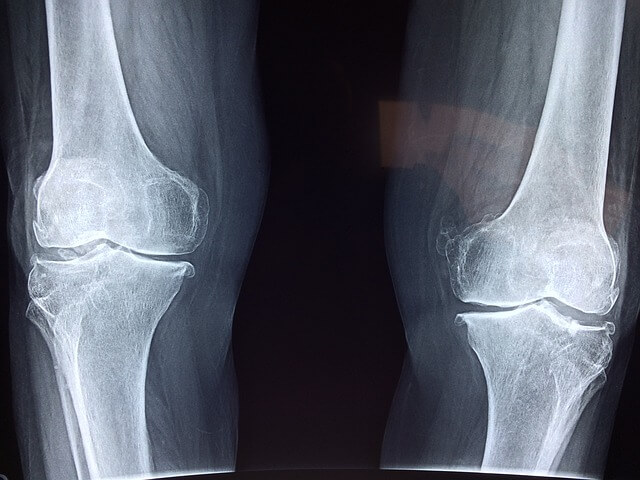

여섯 번째는 관절에 도움을 줍니다.

걷기 운동할 때 그 동작 시 팔과 다리 관절을 사용하기 때문에 신체 구조를 잘 유지할 수 있게 도와줍니다. 그리고 신체의 안정성과 균형성을 지켜주어 낙상으로 인해 생기는 골절과 인대 손상 등을 막아줄 수 있습니다. 또한 걷기 운동은 골관절염에도 도움을 줄 수 있다고 합니다.

일곱 번째는 골다공증에 도움을 줍니다.

골다공증은 누구나 겪을 수 있지만, 특히 여성의 경우 출산 후, 중년기, 폐경 등의 시기에 골다공증을 많이 겪게 됩니다. 그렇기 때문에 여성분들도 걷기 운동을 꾸준히 하게 되면 걷기 운동하지 않은 사람들보다 대퇴골 경부 골절 입을 위험률이 감소한다고 합니다. 또한 걷기 운동할 때 발을 바닥을 디디게 되면 뼈에 긍정적인 자극이 가해지고 근육 수축하면서 골밀도 유지하는 것에 도움을 줄 수 있습니다.